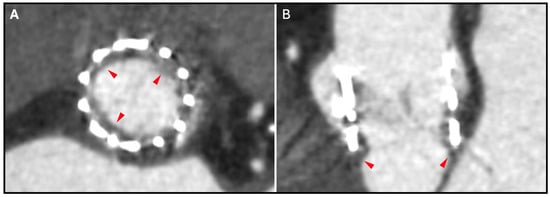

12. Hypoattenuating Leaflet Thickening